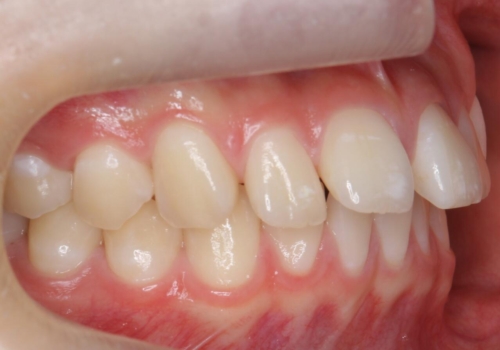

全体矯正ではなく部分矯正で治療することになりました。

その代わり、すき間をすべて閉じるのは難しく、両脇の目立たないところに集めて治療終了しています。

低予算、短期間で治療も終了し、大変満足していただきました。

全体矯正をしていないため、就寝時にリテーナー使用は継続していただくことになっています。